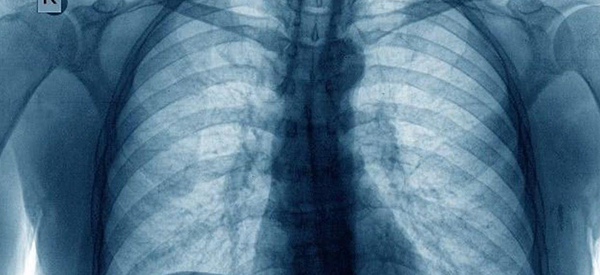

胸透是不可以查乳房硬块的。乳房出现硬块最担心的就是肿瘤尤其是乳腺癌,或者其他良性肿瘤。所以如果发现肿块,需要及时去医院做彩超或者钼靶检查,这两项检查可以准确检查出乳房肿块的问题。胸透检查一般只能检查出心脏,肝脏,肺部,血管有没有出现异常,确诊先天性肺部疾病,以及肺炎、支气管扩张症、肺气肿、肺水肿、肺结核、肺肿瘤等后天肺部疾病。

胸透实际上是查不出来有没有乳腺癌的,因为胸透虽然是检查的胸部,且女性的乳腺也在胸部的范围内。但是胸透影像其实最主要的还是观察两肺,对于乳腺上一点的一些问题是看不到的。女性要每年定期去医院做体检,尤其是乳腺方面的,若疑似乳腺癌要及时的到医院进行乳腺外科的检查,做彩超或钼靶检查确诊。